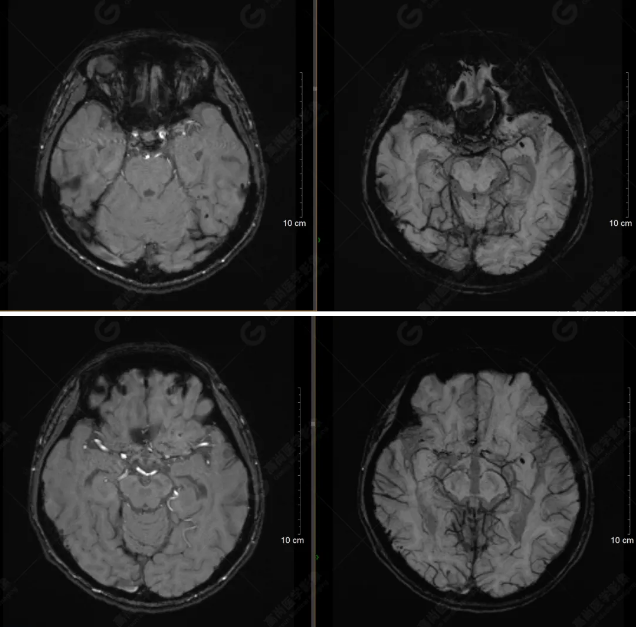

以下是T1WI軸位掃描及矢狀位掃描:

雙側(cè)大腦半球?qū)ΨQ,灰白質(zhì)對比正常,顱內(nèi)未見異常信號影。腦室系統(tǒng)未見擴(kuò)大,中線結(jié)構(gòu)居中。腦溝、裂未見增寬。幕下小腦、腦干未見異常。矢狀位示垂體形態(tài)、大小級信號未見異常。所示左側(cè)乳突內(nèi)見多發(fā)短T1長T2信號影。

顱腦MRI平掃未見明顯異常,左側(cè)乳突內(nèi)積血,建議補(bǔ)充SWI檢查。